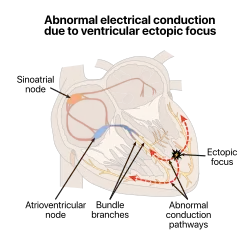

| An illustration of ectopic foci near papillary muscles in the left ventricle | |

An ectopic pacemaker, also known as ectopic focus or ectopic foci, is a group of excitable cells that causes a premature heart beat known as an ectopic beat, outside the normally functioning SA node of the heart. It is thus a cardiac pacemaker that is ectopic, producing an ectopic beat. Acute occurrence is usually non-life-threatening, but chronic occurrence can progress into tachycardia,[1] bradycardia or ventricular fibrillation.[2] In a normal heart beat rhythm, the SA node usually suppresses the ectopic pacemaker activity due to the higher impulse rate of the SA node. However, in the instance of either a malfunctioning SA node or an ectopic focus bearing an intrinsic rate superior to SA node rate, ectopic pacemaker activity may take over the natural heart rhythm.[3] This phenomenon (an intrinsically slower pacemaker activity being unmasked by failure of faster pacemaker tissue 'upstream') is called an escape rhythm, the lower rhythm having escaped from the dominance of the upper rhythm. As a rule, premature ectopic beats (i.e. with a shorter than the prevailing preceding R-R' interval) indicate increased myocyte or conducting tissue excitability, whereas late ectopic beats (i.e. with a prolonged preceding R-R' interval) indicate proximal pacemaker or conduction failure with an escape 'ectopic' beat.

An ectopic pacemaker can reside within a part of the electrical conduction system of the heart, or within the muscle cells of the atria or ventricles. When an ectopic pacemaker initiates a beat, premature contraction occurs. A premature contraction will not follow the normal signal transduction pathway, and can render the heart refractory or incapable of transmitting the normal signal from the SA node. Location of the pacemaker can also change its effect on the SA node and its rhythm. An ectopic pacemaker located in the atria is known as an atrial pacemaker and can cause the atrial contraction to be faster.[10] An ectopic pacemaker situated near the AV node and the septum is known as a junctional pacemaker.[11] The pacemaker that is operating in the ventricles is known as the ventricular.[12] Other such ectopic pacemakers can even lie within the pulmonary vein and thoracic vein walls.[13][14]